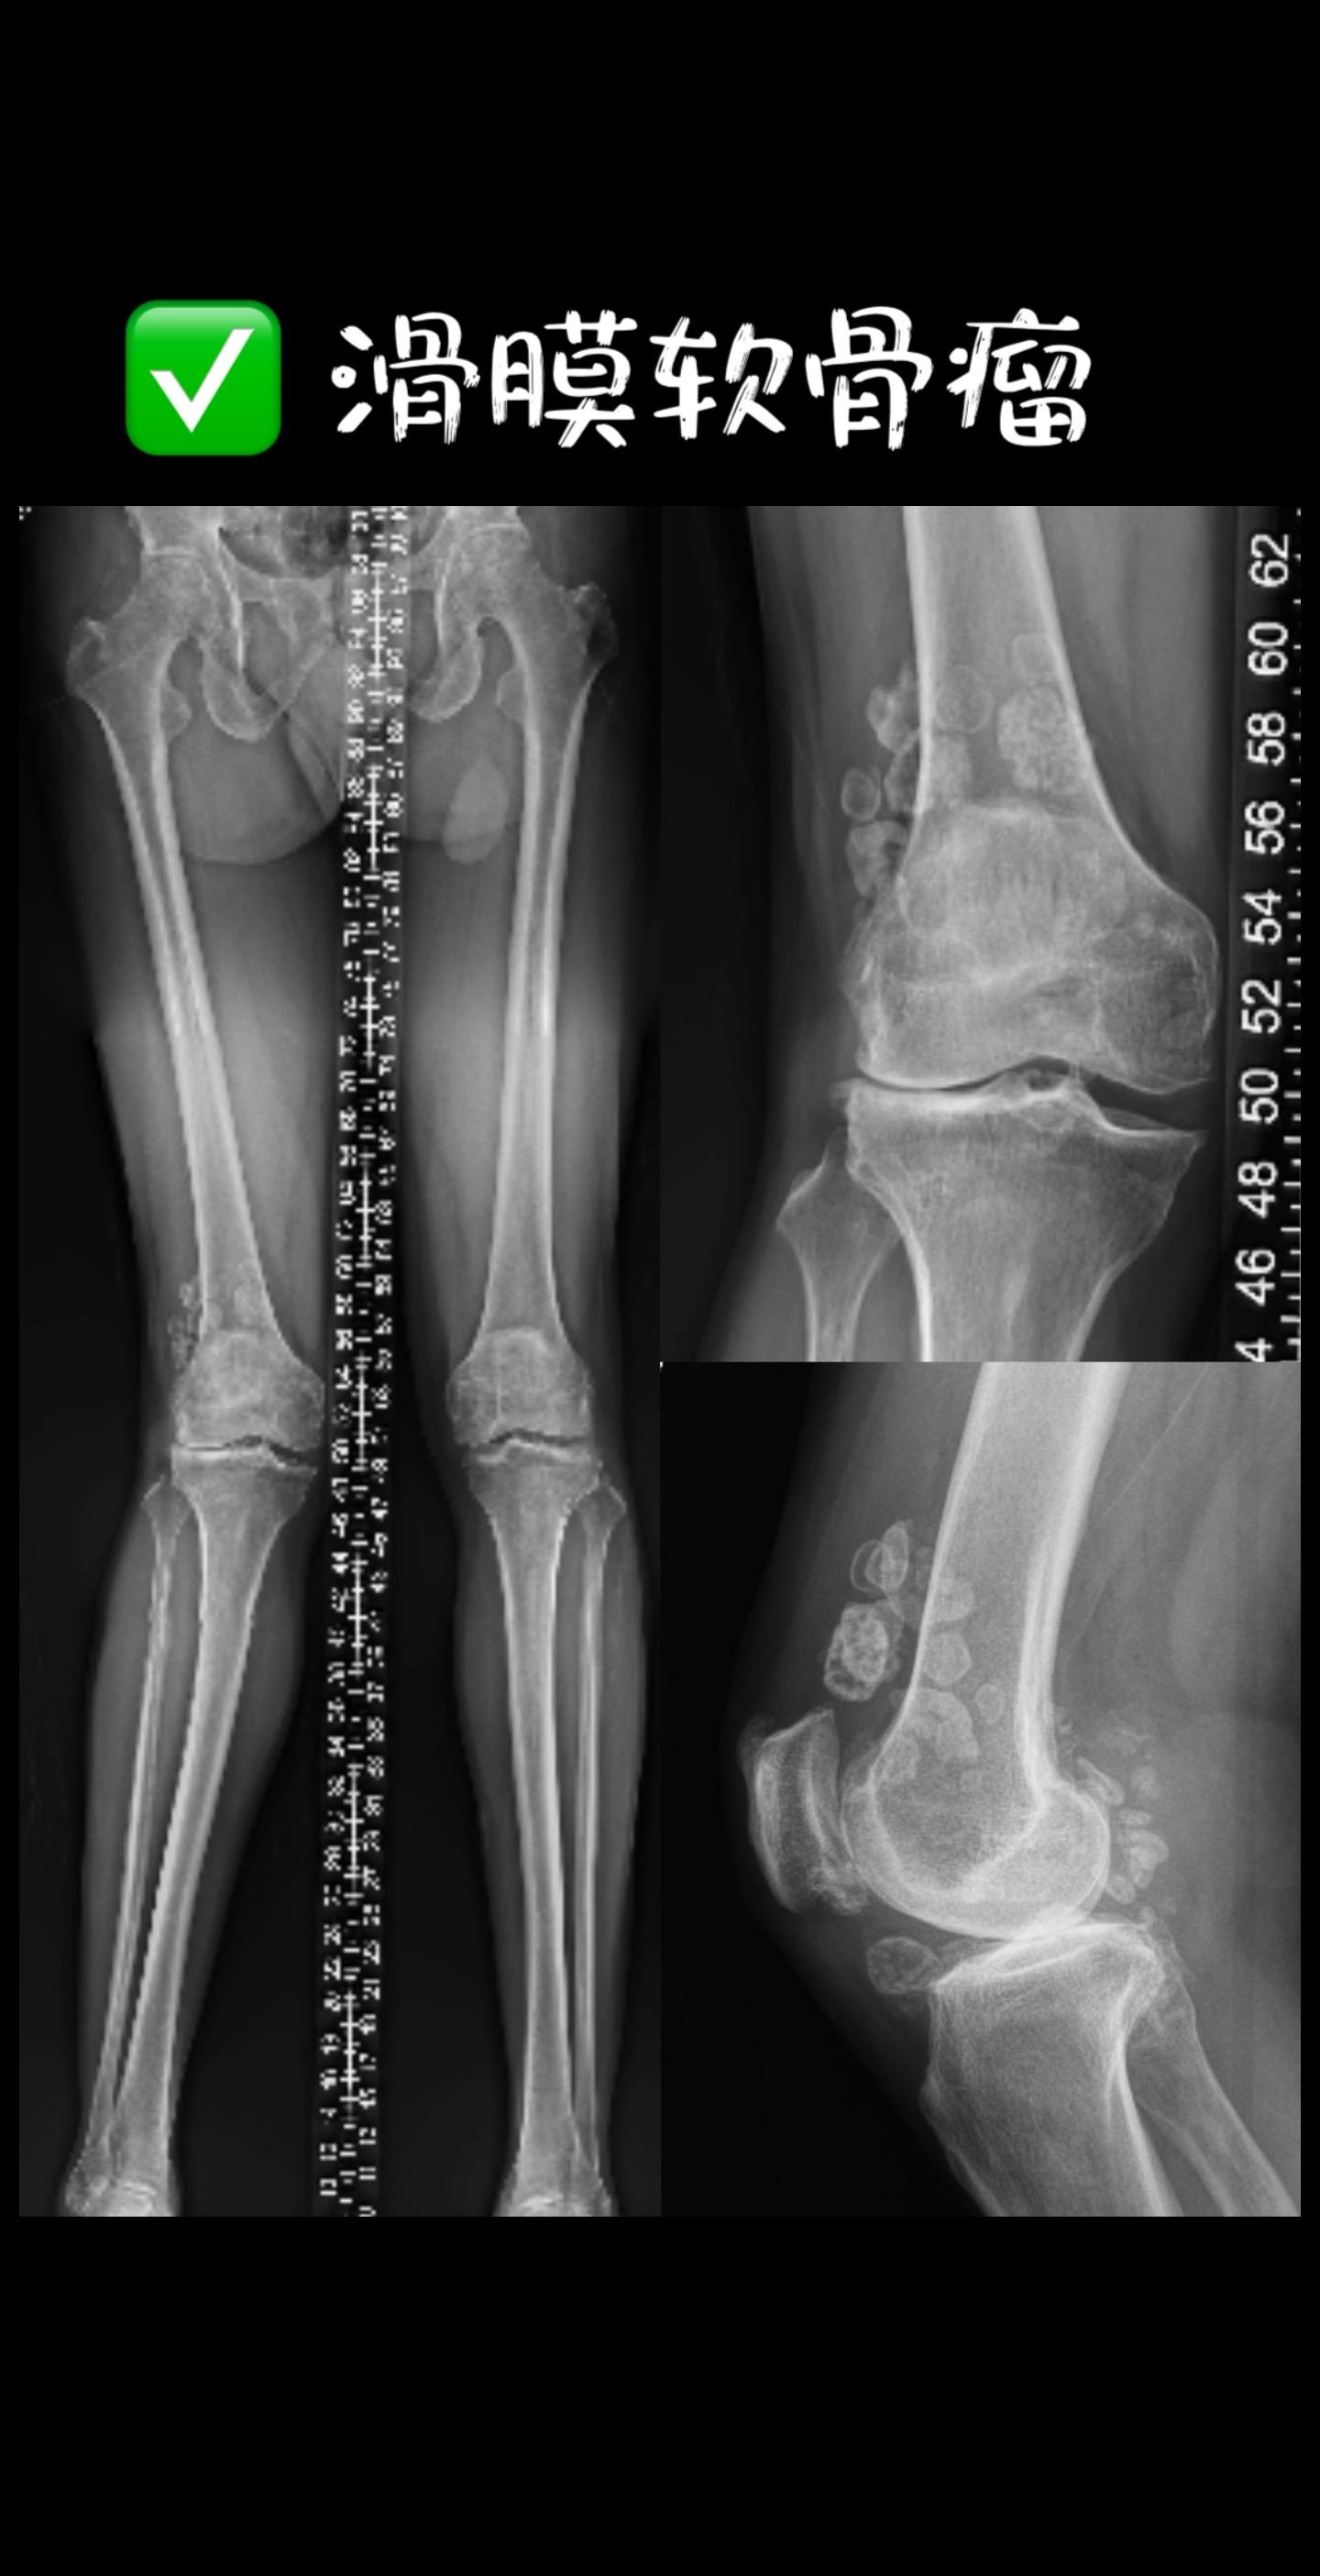

滑膜软骨瘤。膝关节滑膜软骨瘤病3大特征: 1️⃣ 游离体像‘石榴籽’散落关节 2️⃣ 滑膜从‘地毯’变‘鹅卵石路’ 3️⃣ 不治疗→100%继发骨关节炎!